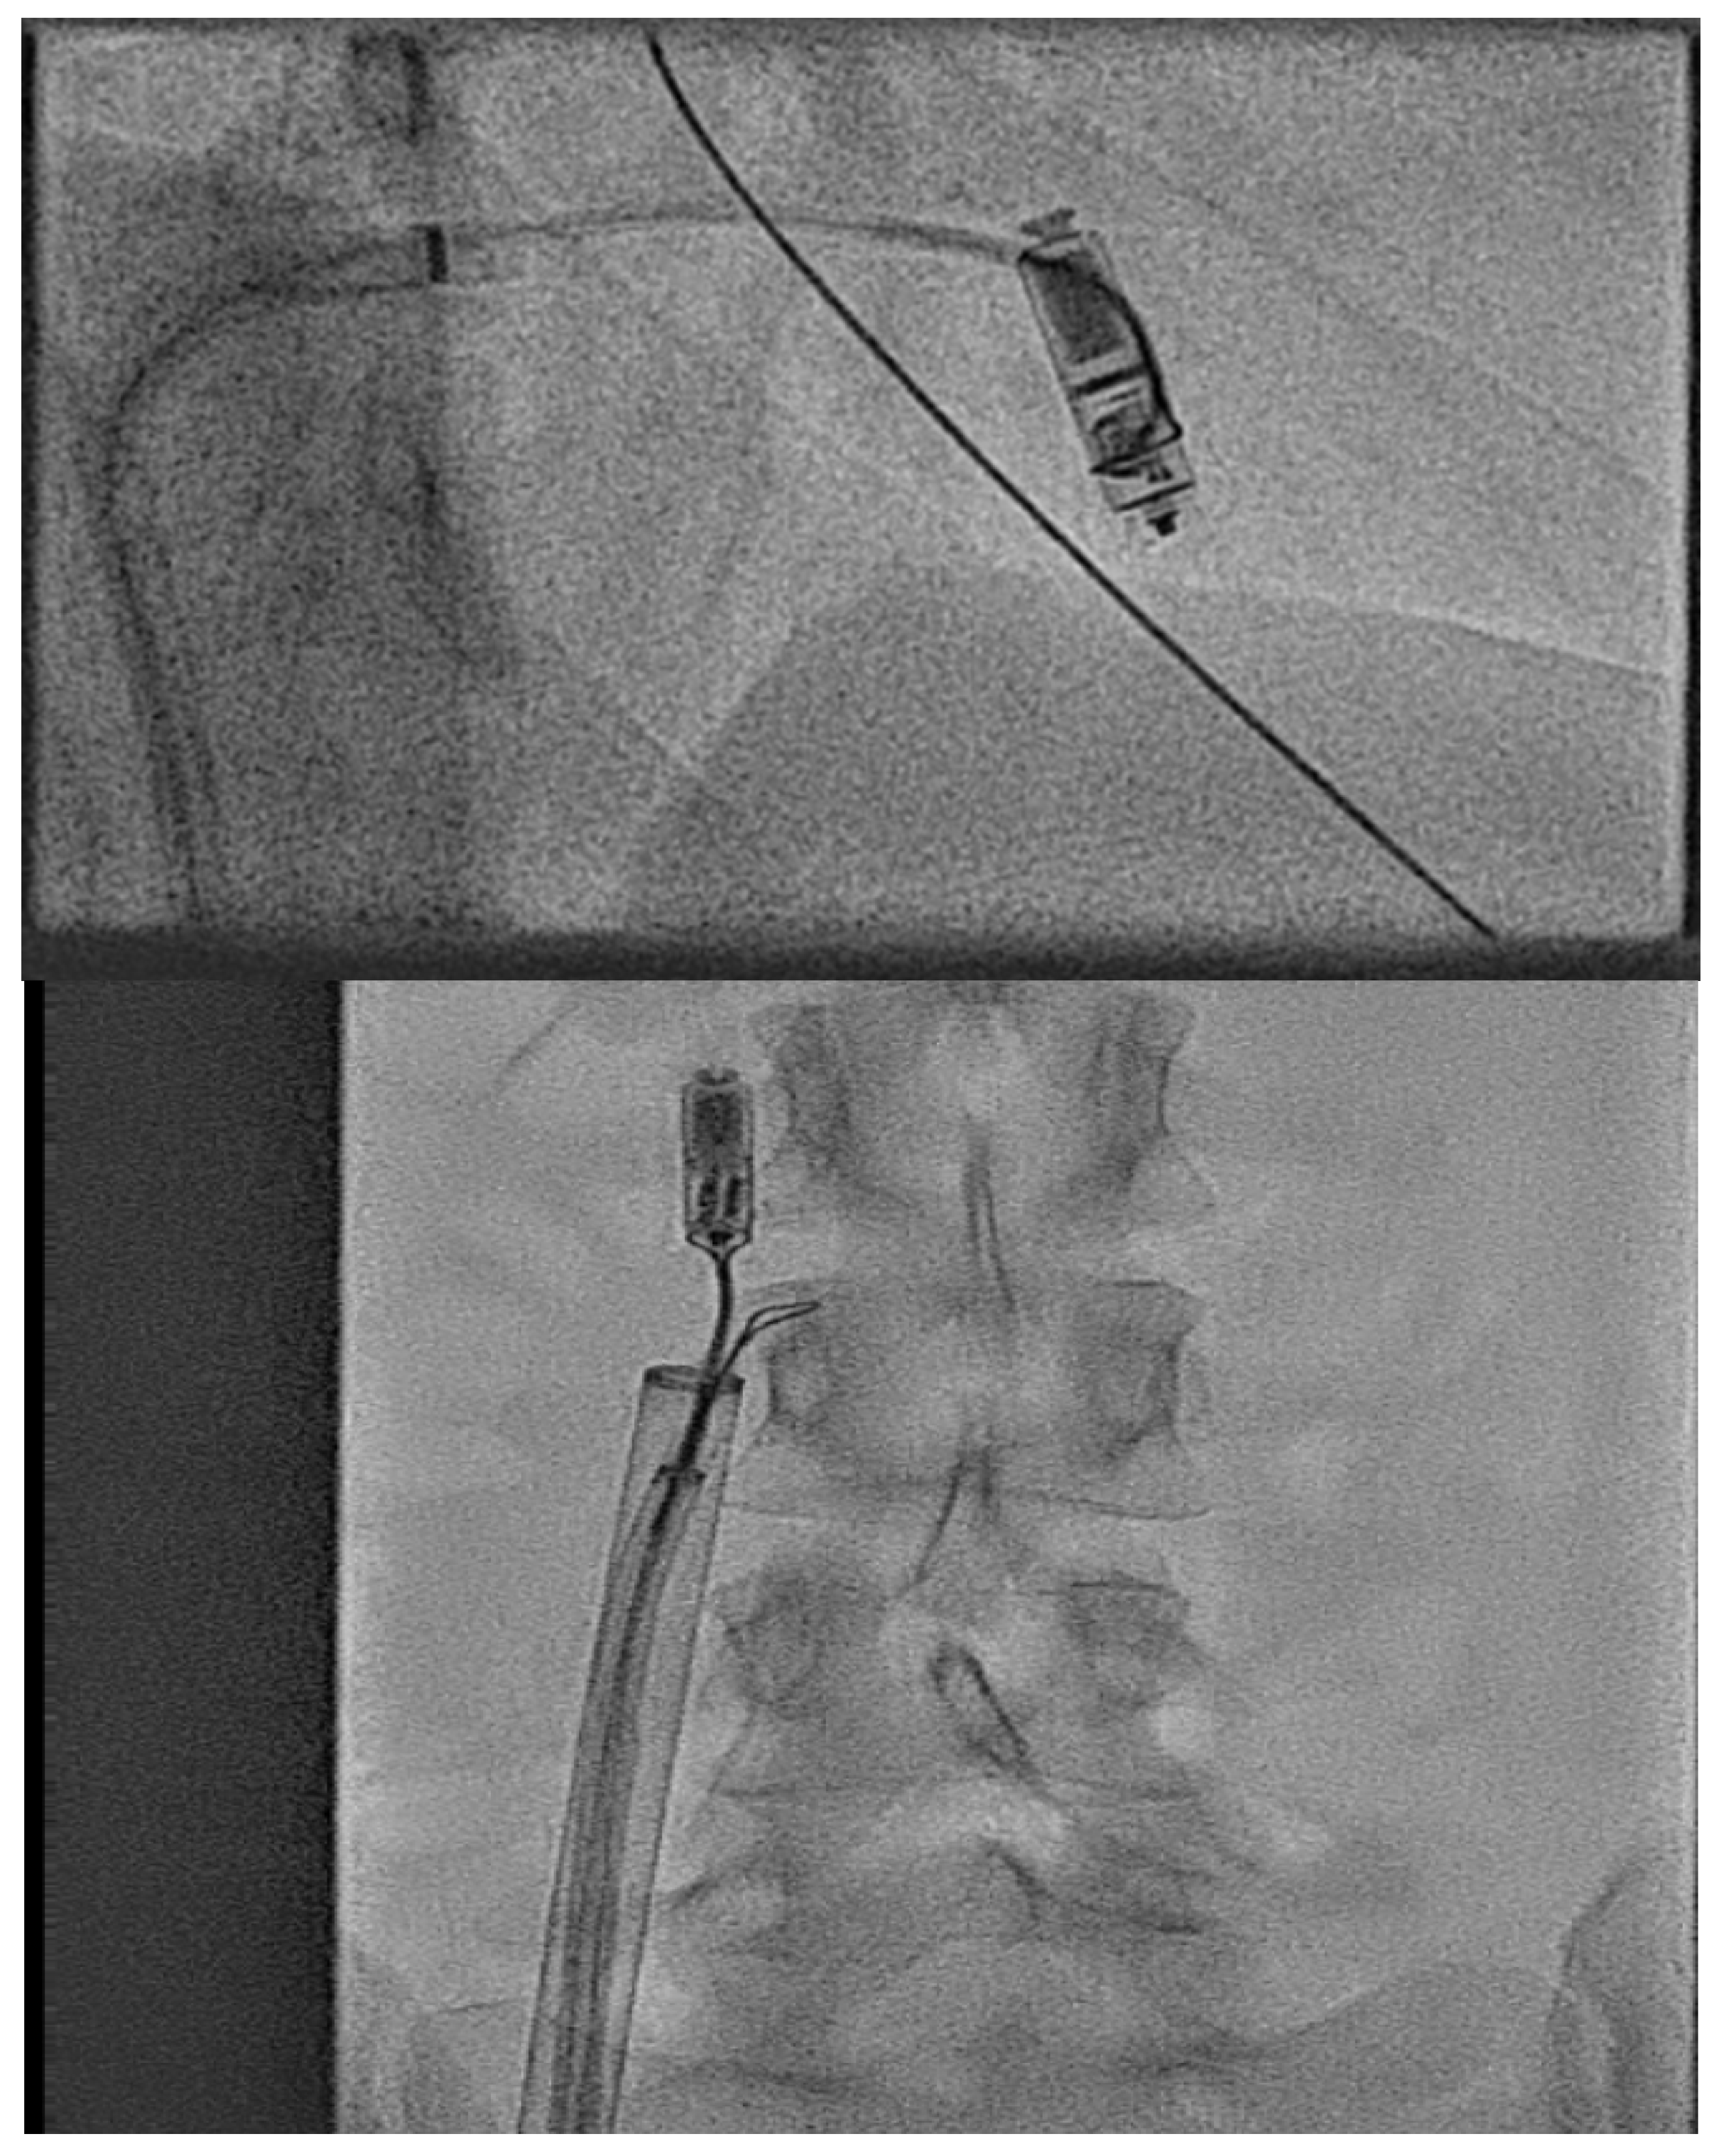

- Calvert, P.; Yeo, C.; Rao, A.; Neequaye, S.; Mayhew, D.; Ashrafi, R. Transcarotid implantation of a leadless pacemaker in a patient with Fontan circulation. Hear. Case Rep. 2023, 9, 53–58. [Google Scholar] [CrossRef]

- Hayle, P.; Altayeb, F.; Hale, A.; Rao, A.; Ashrafi, R. Case report demonstrating novel approaches for leadless pacemaker implantation in the single ventricle heart. Eur. Heart J. Case Rep. 2025, 9, ytaf146. [Google Scholar] [CrossRef]

- Goulden, C.J.; Khanra, D.; Llewellyn, J.; Rao, A.; Evans, A.; Ashrafi, R. Novel approaches for leadless pacemaker implantation in the extra-cardiac Fontan cohort: Options to avoid leaded systems or epicardial pacing. J. Cardiovasc. Electrophysiol. 2023, 34, 2386–2392. [Google Scholar] [CrossRef]